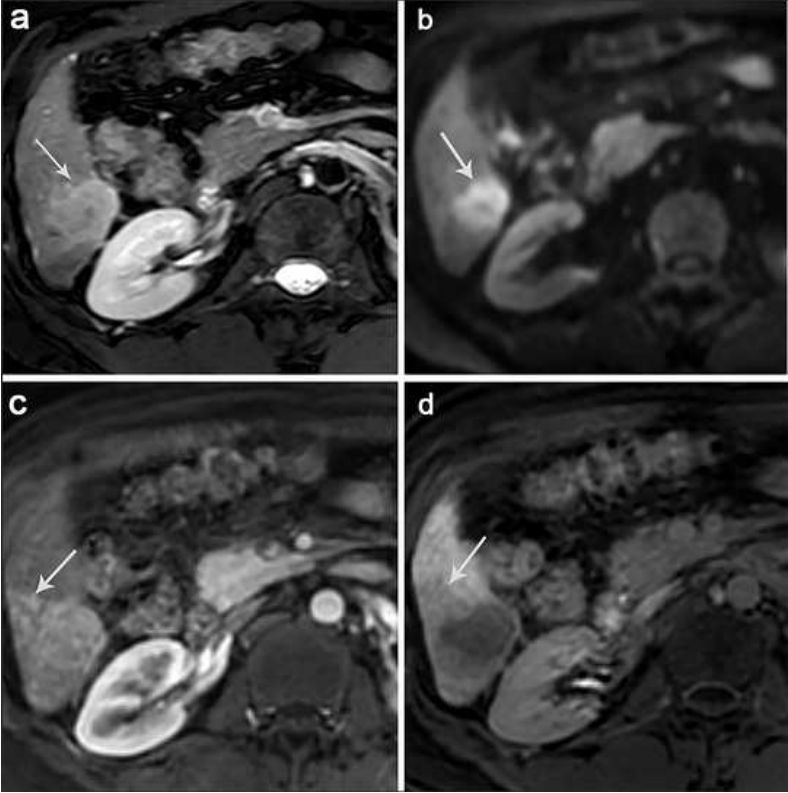

After 7 months from curative resection for HCC, intrahepatic tumor recurrence was detected by follow-up MR imaging. An approximately 2.0 cm mass was seen in S8 (arrow). (a) T2 WI showed a moderately hyperintense lesion with smooth margin. (b) Diffusion restricted on DWI. (c) Dynamic contrast-enhanced scans showed enhancement of the lesions (arrow) in the arterial phase, but no enhancement in the central necrotic area. (d) The mass showed peritumoral hypointensity (arrowheads) on HBP.